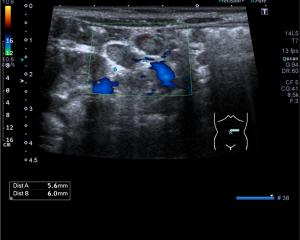

Dopplerovské ultrazvukové vyšetření navíc umožňuje kvalitativně i kvantitativně posoudit nález na cévním řečišti, zejména zhodnotit přítomnost uzávěrů cév či posoudit stupeň jejich zúžení.

Zjednodušeně řečeno je indikací ultrazvukového vyšetření posouzení morfologického nálezu ve vyšetřované oblasti. Tedy odpověď na otázku, zda je v problematické oblasti něco divného a pokud ano, o co se jedná. Ultrazvuk je velmi vhodnou metodou pro posouzení orgánů v břišní dutině a v měkkých tkáních krku i jinde na těle, naopak je prakticky nepoužitelný pro posouzení plic a kostí. Dopplerovský ultrazvuk umožňuje hodnotit nález na cévách, zejména posoudit jejich průchodnost a eventuelně stupeň zúžení, které bývá nejčastěji na podkladě aterosklerózy (kornatění tepen).

Vyšetření provádí erudovaný lékař, který pro danou vyšetřovanou oblast zvolí vhodnou ultrazvukovou sondu a nastaví optimální parametry přístroje. Pacient při vyšetření leží na vyšetřovacím stole a dodržuje pokyny lékaře. Nejčastěji se vyšetření provádí vleže na zádech, na břiše nebo na boku. Kůže pacienta se ve vyšetřované oblasti pokrývá vrstvou gelu pro sonografii. Lékař plynule pohybuje po pacientově těle ve vyšetřované oblasti ultrazvukovou sondou a při tom sleduje obraz na monitoru. Vyšetření se provádí v různých rovinách daných postavením sondy, někdy i v různých polohách pacienta. Během vyšetření lékař v případě potřeby provádí různá měření. Při vyšetření asistuje vyškolená sestra, která pomáhá především s odstrojením a uložením pacienta, provádí administrativní úkony a řídí objednávání pacientů. Před vyšetřením sestra nebo lékař vysvětlí pacientovi stručně, jak vyšetření probíhá a co je jeho cílem, eventuelně rozptýlí případné obavy pacienta z vyšetření. Na závěr vyšetření pak lékař pacientovi co nejsrozumitelněji vysvětlí zjištěný nález, jeho závažnost a případné další důsledky. Obrazová dokumentace je zhotovena tiskem na speciální papír, eventuelně je provedena digitální archivace obrazu.